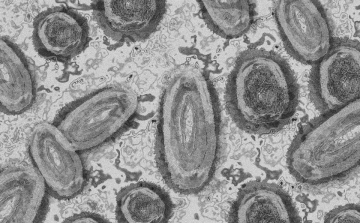

2022. Augusztus 25. 11:02, csütörtök | Külföld

Egy 3 év alatti gyermek fertőződött meg majomhimlővel Belgiumban